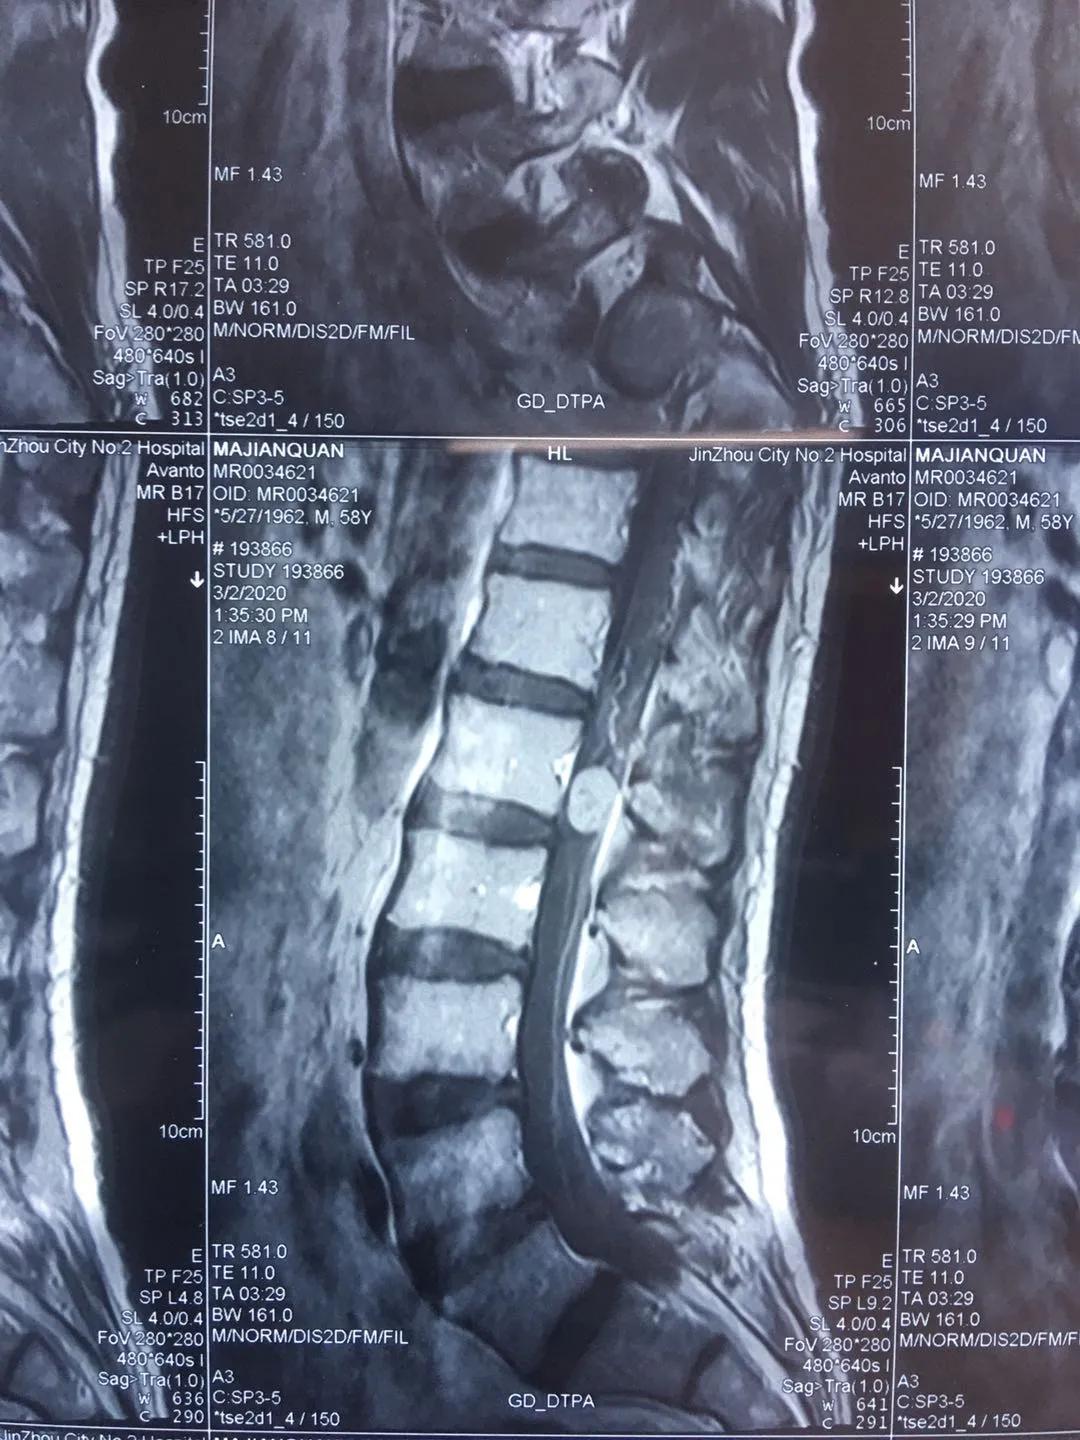

患者马先生今年58岁,于2年前无明显诱因出现左下肢抽痛,呈间歇性发作,以双下肢后明显,行走时有针刺样疼痛,伴双下肢麻木不适,2个月前马先生上述症状加重,行脊柱MRI平扫+增强提示腰椎管内肿瘤,神经鞘瘤可能性大,患者慕名来到市二院骨八科找到田晓东博士,请求田晓东博士为他解除痛苦。

经骨八科田晓东主任及神经外科黄涛主任等医务人员讨论认为:患者手术指征明确,并无明显手术禁忌,建议尽快行手术治疗。手术拟行腰椎后路切开椎弓根钉棒系统内固定+椎板切除+腰椎管内肿瘤切除术联合手术治疗。术后,患者症状改善明显,双下肢抽搐痛伴麻木症状逐渐改善,肢体力量也逐渐恢复。